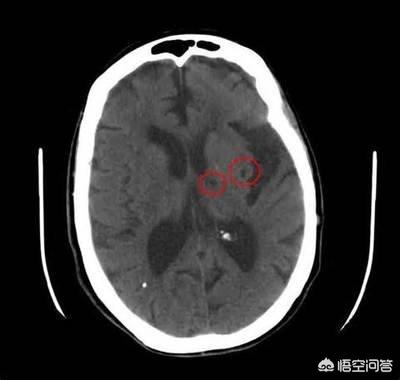

海綿状梗塞は脳梗塞である」という発言は、時折、頭部のCTやMRIで単発または多発の海綿状梗塞が見つかるため、アスピリンやスタチンなどを投与されている多くの人々を恐怖に陥れている。わずか数ミリの大きさの梗塞巣に対処することが本当に必要なのだろうか?

空洞性脳梗塞は、大脳半球および脳幹の深部白質に発生する虚血性微小脳梗塞である。梗塞巣は不規則な円形、卵形、または細長い形をしており、その直径は数ミリである。以前は、この現象はヒトの脳の病理解剖時にのみ検出されていた。CTやMRIが普及し、技術が進歩するにつれて、ラクナ脳梗塞が発見される確率が高くなった。

脳梁性脳梗塞とは、大脳半球や脳幹に存在する小さな穿通動脈の内腔が、様々な原因による血管壁の病変によって閉塞することによって生じる小さな梗塞病巣である。

これらの小深動脈は脳動脈の終末枝であり、血液供給が限られているため、虚血による壊死の範囲も限られており、通常は15mm程度の小さな病変にとどまる。そのため、ほとんどの場合、症状はなく、壊死した部分だけが吸収され、小さな嚢腔が残ることがある。